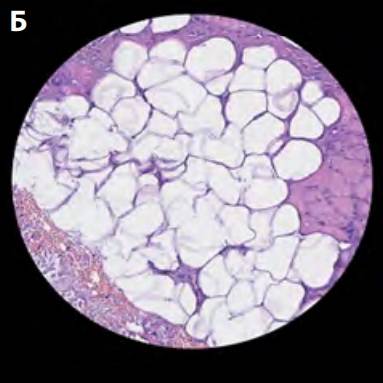

Через 1 нед. и 1 мес. после процедуры Morpheus8 у пациентки были взяты образцы тканей субментальной зоны. Наблюдались следующие структурные изменения состояния жировой ткани и соединительнотканных перемычек:

- через 1 нед. – признаки лизиса адипоцитов;

- через 1 мес. – признаки распада адипоцитов, уменьшение среднего размера адипоцитов на 37,6%, уплотнение и реструктуризация коллагеновых волокон (плотность возросла на 42,4%), более 62% волокон имеют строгую ориентацию по сравнению с исходным состоянием (34%) (рис. 14).